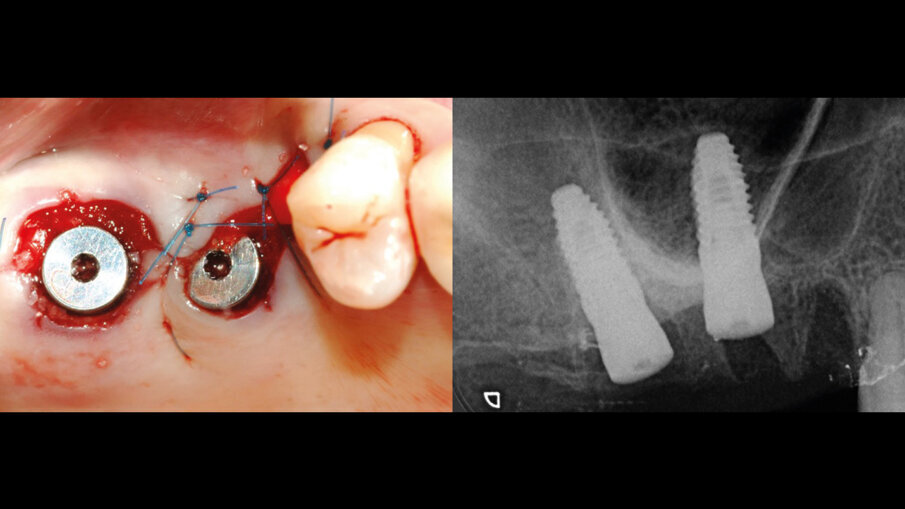

Il caso clinico tratta di una donna di 63 anni che giunge alla nostra osservazione presso il centro odontoiatrico civitali di Milano, presentando gli elementi 26 e 27 non recuperabili e richiedendo una riabilitazione fissa (Fig. 1). Verificata la presenza di osso residuo sufficiente a garantire il corretto posizionamento implantare, nonostante una condizione ossea discretamente compromessa, abbiamo ritenuto che con appropriata tecnica chirurgica estrattiva attua a salvaguardare i profili ossei e il setto inter-radicolare abbinata a una macromorfologia implantare idonea, si potesse ottenere un buon livello di stabilità primaria. Per ripristinare e mantenere i volumi ossei si è quindi optato per un posizionamento implantare immediato associato a un mantenimento di volume osseo della cresta ossea vestibolare. Per colmare lo spazio residuo formatosi successivamente all’estrazione delle radici vestibolari degli elementi si è optato per l’utilizzo di un innesto osseo costituito da un cilindro di pasta ossea liofilizzata di origine equina (Bio-Gen Putty, Bioteck Spa) protetto da una matrice collagenica tridimensionale (XC COLLAGEN Xenomatrix, Bioteck Spa).

Il giorno prima dell’intervento, la paziente veniva sottoposta a terapia antibiotica con Amoxicillina e Acido Clavulanico compresse da 1 gr ogni 12 ore. Il giorno dell’intervento veniva eseguita la profilassi antibiotica 1 ora prima dell’inizio con 875/125 mg di Amoxicillina+ Acido Clavulanico e veniva praticata l’anestesia locale con Articaina + adrenalina 1:100.000. Quindi si procedeva all’estrazione dei due elementi compromessi (Fig. 2) e si provvedeva alla preparazione del sito implantare all’interno della radice palatina; gli autori considerano questa la sede di elezione ove la zona del setto inter-radicolare non fosse idonea ad accogliere l’impianto. Una volta preparati i tunnel implantari nei siti 26 e 27, venivano inseriti due impianti 4.3 x 10 mm (IDI evolution Tiger) (Fig. 3). La stabilità implantare veniva misurata mediante il rapporto e lo scambio di energia tra la superficie di contatto ossea e l’impianto ottenendo un valore oggettivo (Newton/cm) che rappresenta la stabilità implantare (TMM3 IDI evolution) (Fig. 4).

Fig. 1 - Visione occlusale che mostra gli elementi 26-27 irrecuperabili. Sotto, l’RX iniziale.

Fig. 3 - Inserimento dei due impianti 4.3 x 10 mm (IDI evolution Tiger) all’interno dello spazio alveolare.

Fig. 8 - Chiusura dei lembi e guarigione per seconda intenzione. L’RX conferma il corretto posizionamento implantare.